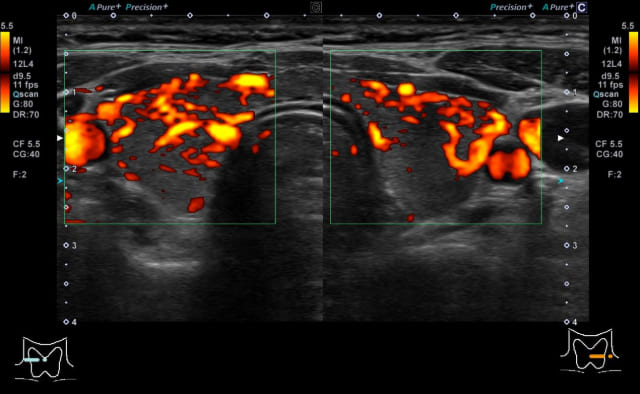

甲状腺ホルモンが過剰に出る病気で、腫れに加え、動悸や体重減少などの症状を伴うことがあります。

エコー所見では、甲状腺のびまん性腫大と、甲状腺辺縁がやや黒っぽくなり、甲状腺内部の血流増加と栄養血管の血流量・速度が上昇することが特徴的です。